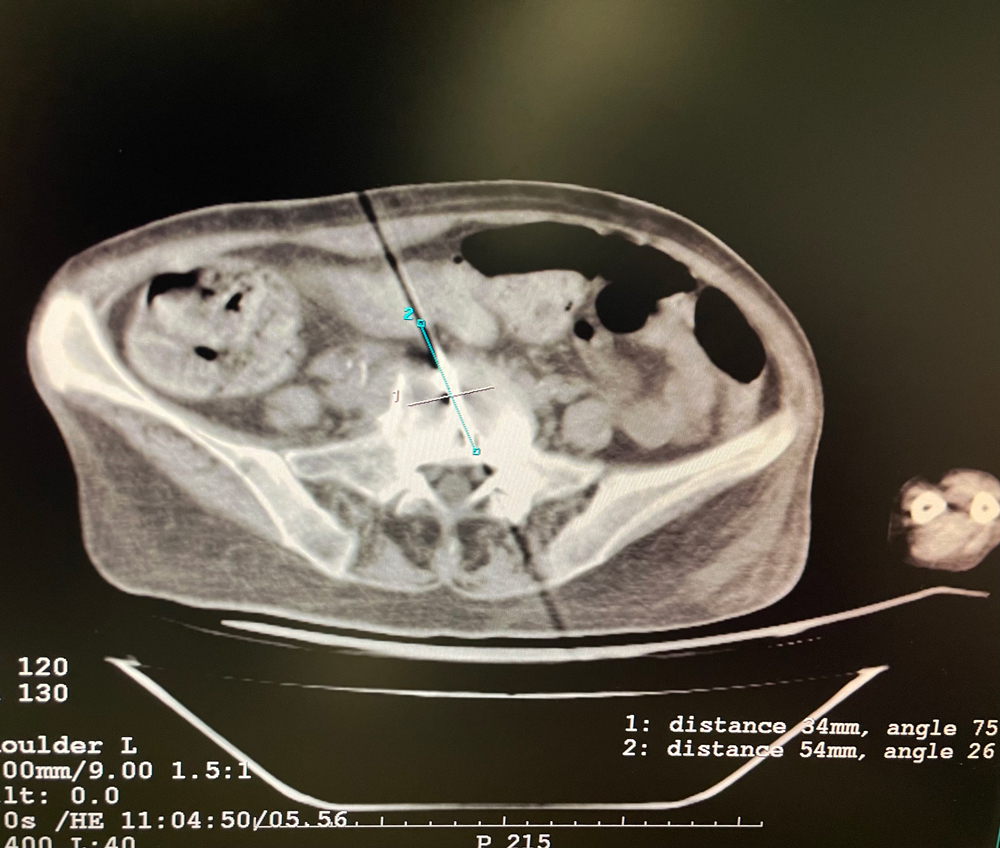

女,56歲,肺轉移瘤,骶骨、左側肋骨各一轉移灶,病灶大小均為5cm。骶骨轉移灶、肋骨轉移灶各進行2個凍融循環。患者術后狀況良好。

女,42歲,復發性脂肪瘤,病灶位于右側膝關節,直徑大小13cm。采用雙針方案,共進行6個凍融循環,最大冰球直徑達8.2cm,術中多方位治療全面覆蓋病灶范圍。患者術后狀況良好。